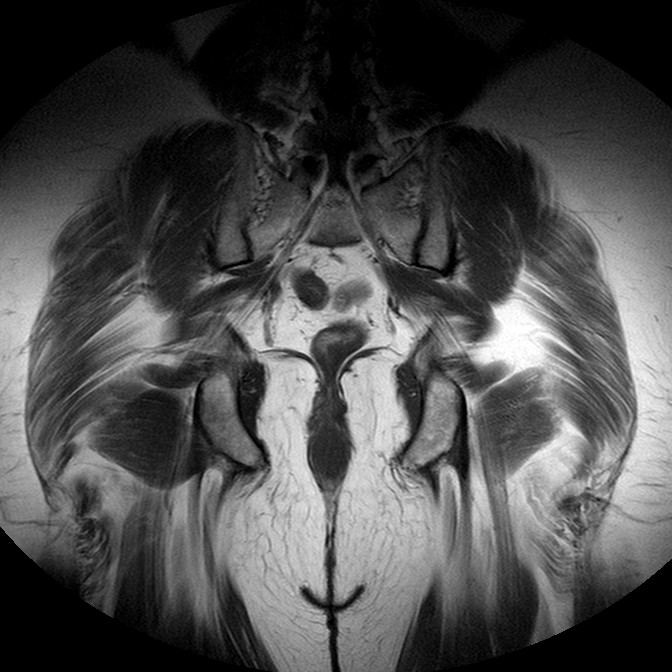

Esami: RMN BACINO

T1w TSE

Evidenti e simmetriche alterazioni osteofitosiche in regione coxo femorale con riduzione delle rime articolari. Degenerazione completa del cercine glenoideo. Non attuali segni di versamento articolare. Non segni di edema osseo che escludono attuale algodistrofia od osteonecrosi. Lieve e simmetrica riduzione del trofismo della muscolatura glutea.